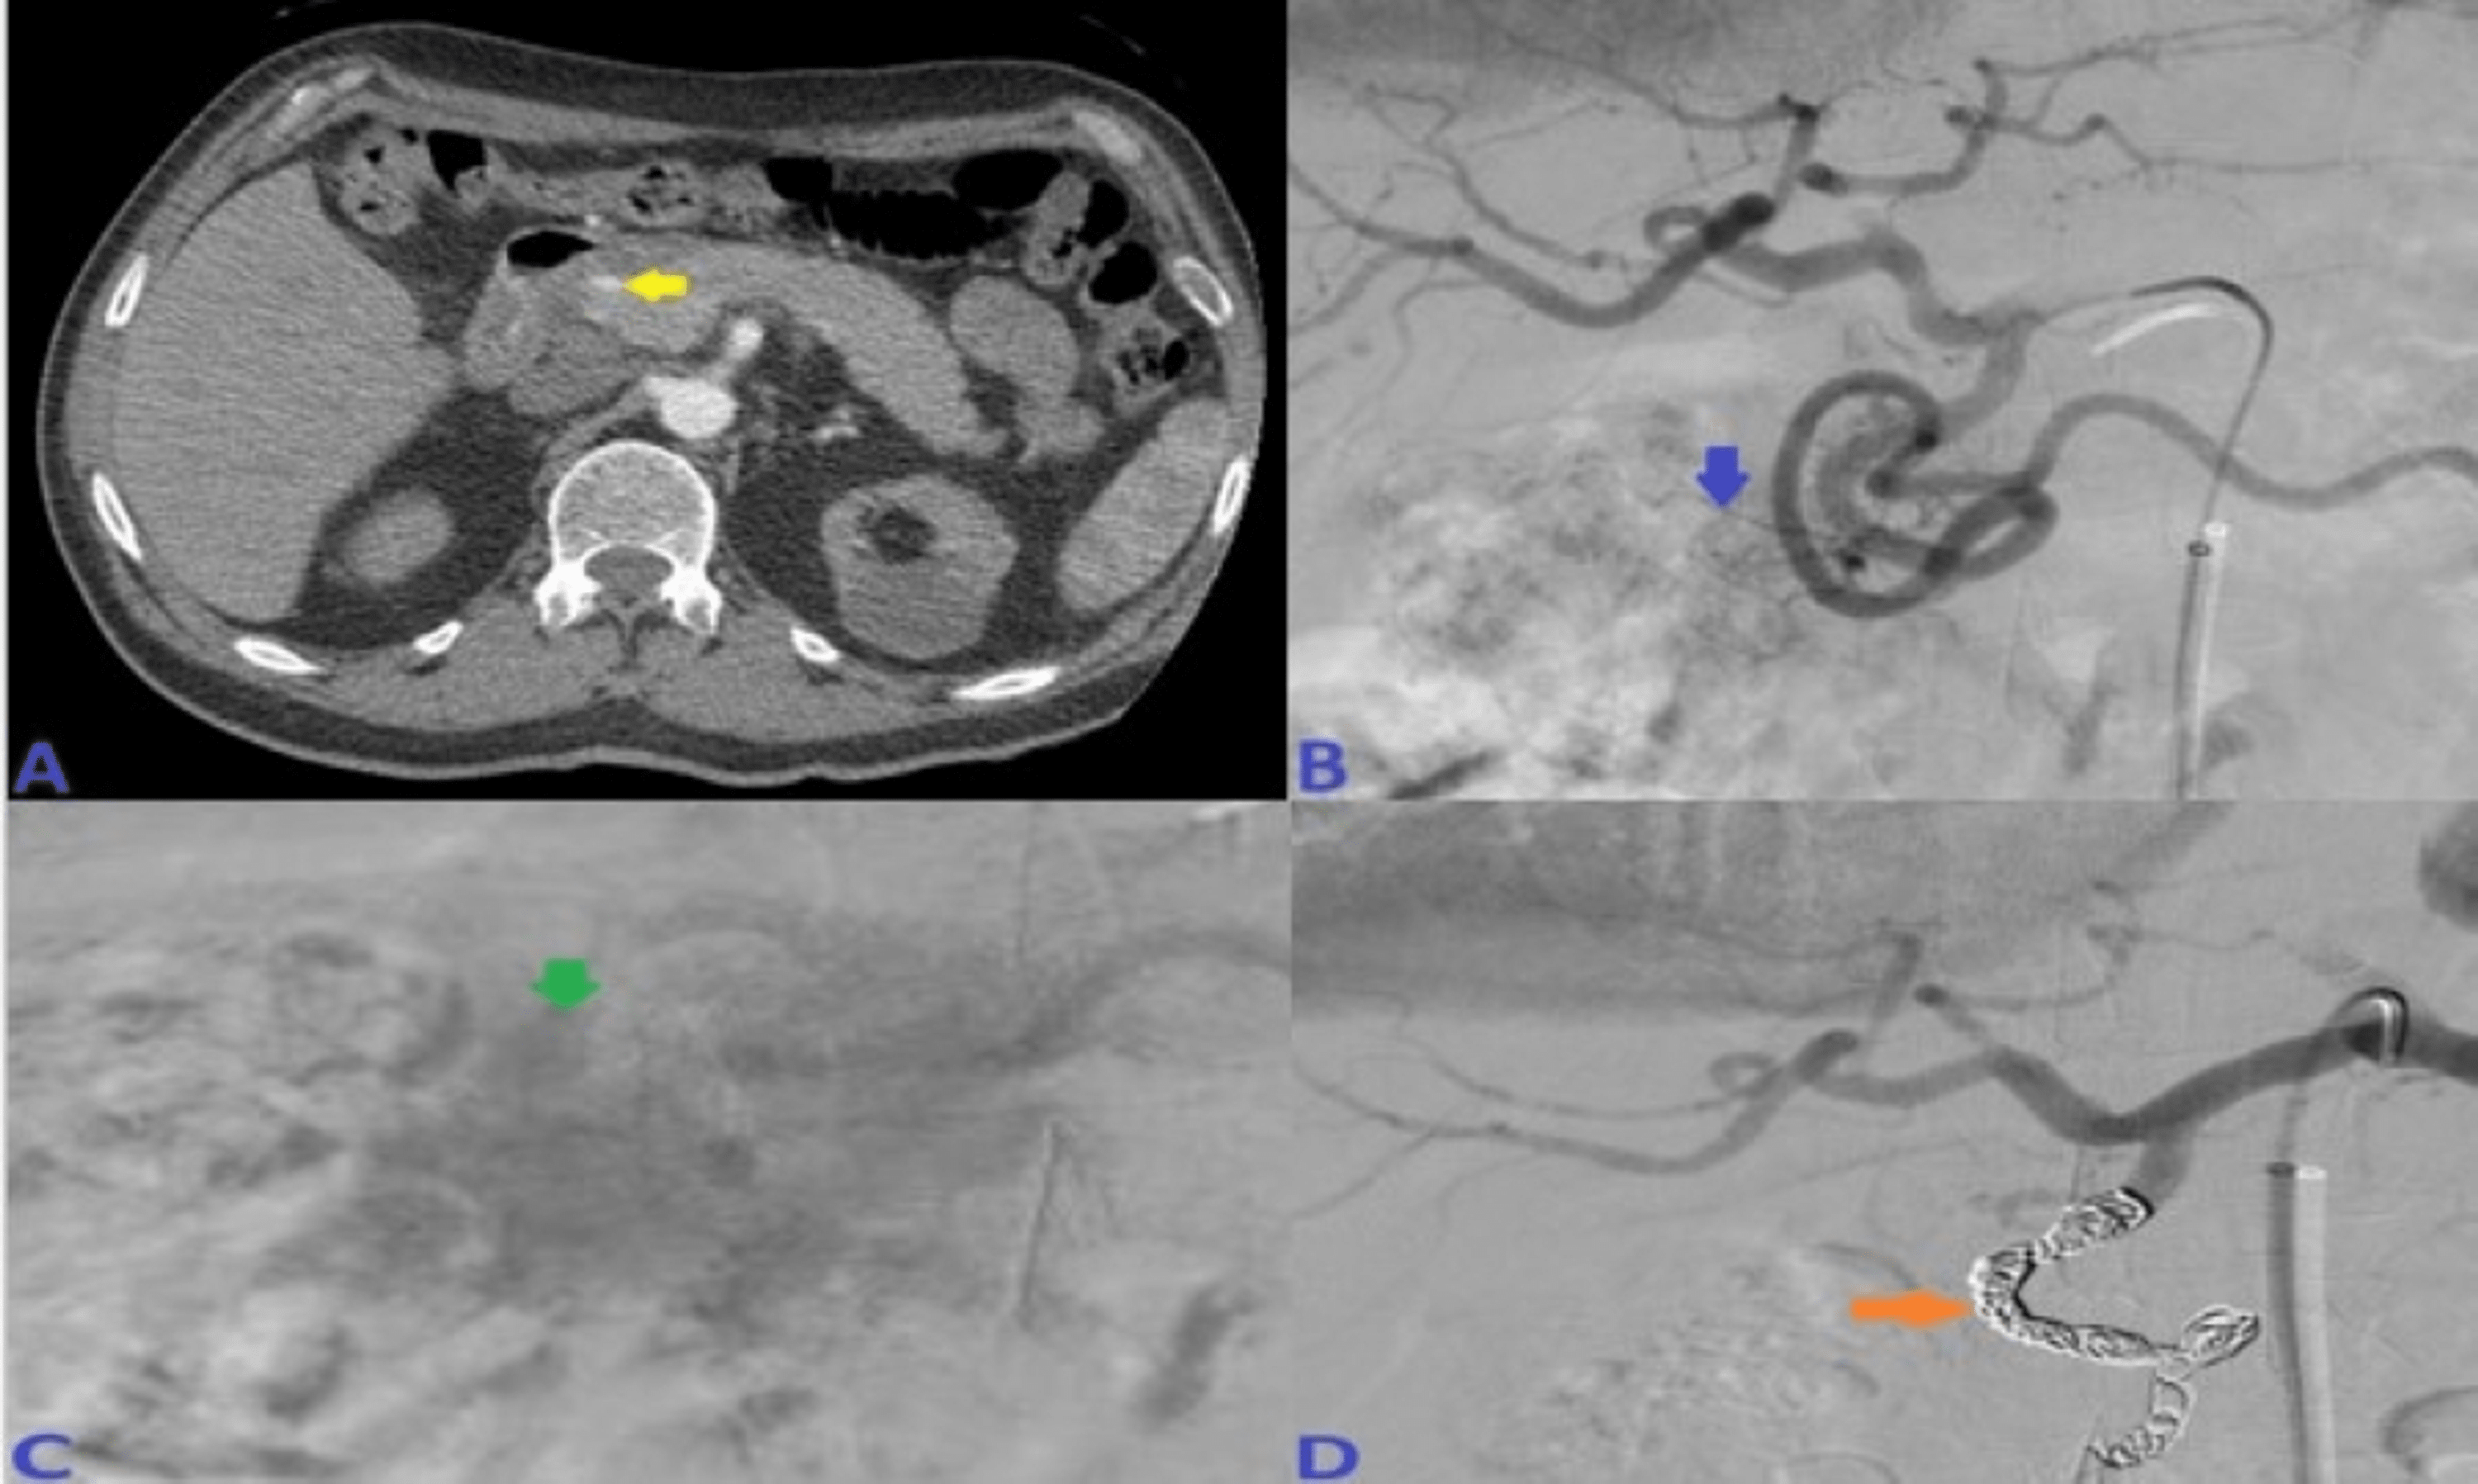

Successful coil embolization of gastroduodenal artery aneurysm. Arrow Embolization Coils Abdomen Pushable coils are the dominant embolic agent used in both upper and lower gi hemorrhage. This report describes our experience of coil. Coils come in two broad categories: Embolization coil migration to the gastrointestinal tract is a rare complication. Coil embolization of the distal and proximal gda (with gelatin sponge in the arterial trunk), including the anterior and posterior superior.. Embolization Coils Abdomen.

Embolization with two coils in the gastroduodenal artery (blue arrow Embolization Coils Abdomen Coil embolization of the distal and proximal gda (with gelatin sponge in the arterial trunk), including the anterior and posterior superior. Embolization coil migration to the gastrointestinal tract is a rare complication. The main limitation of coils is malposition or nontarget coil migration. Healthcare providers use endovascular coiling to block blood flow into an aneurysm. Embolization coils can migrate to. Embolization Coils Abdomen.